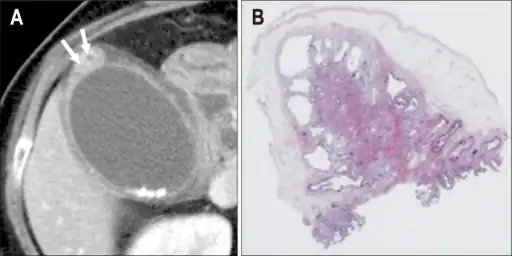

Individual with adenomyomatosis a) Axial computed tomography image b) photomicrograph- Adenomyomatosis of the gallbladder as seen on ultrasound[7]

Non-contrast abdominal ultrasound and contrast-enhanced ultrasound (CEUS) of adenomyomatosis of the gallbladder:[8]

a The fundus of the gallbladder wall was thickened and the GB wall was obscure.

b The intramural echogenic foci were detected by high frequency transducer.

c CEUS—arterial phase (22 s) —heterogeneous hyper-enhancement and wall was intact.

d CEUS—venous phase (34 s) the anechoic spaces were more clear.